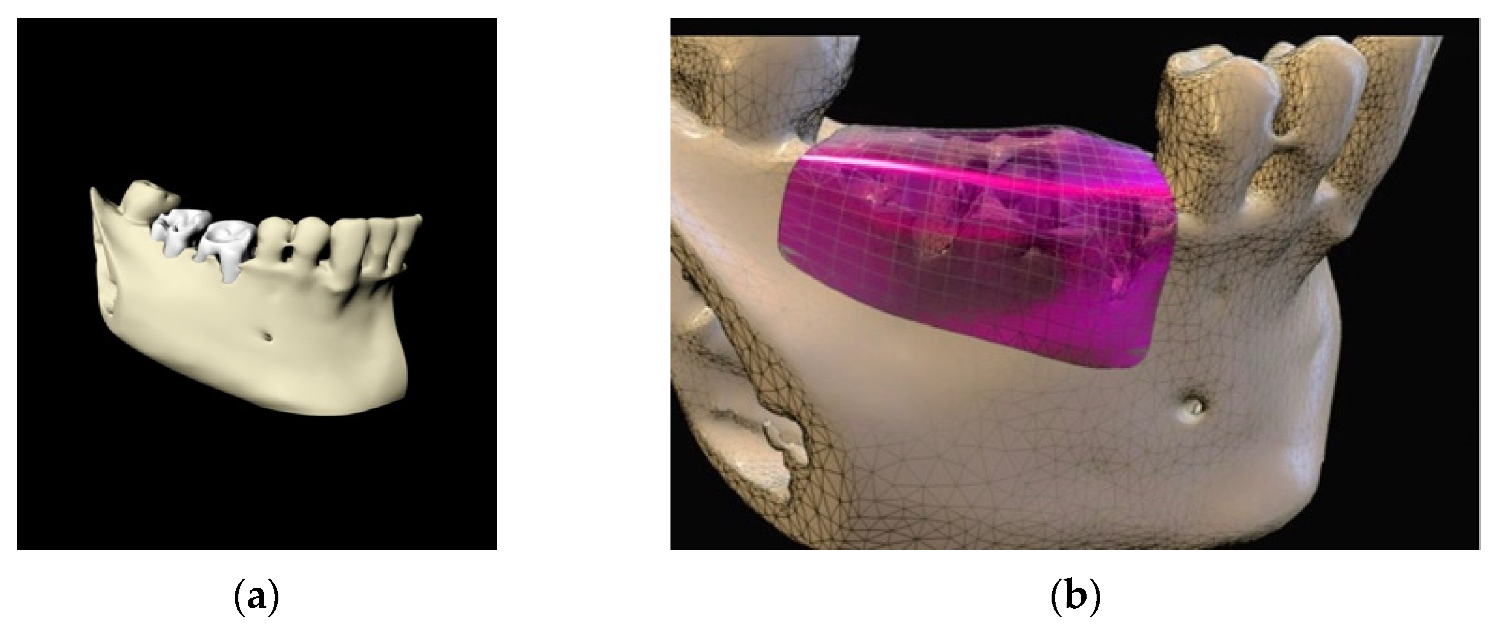

3. Clot Management and Titanium Foil: Biological Principles

4. Case Series